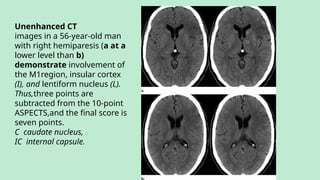

Unenhanced CT

images in a 56-year-old man

with right hemiparesis (a at a

lower level than b)

demonstrate involvement of

the M1region, insular cortex

(I), and lentiform nucleus (L).

Thus,three points are

subtracted from the 10-point

ASPECTS,and the final score is

seven points.

C caudate nucleus,

IC internal capsule.